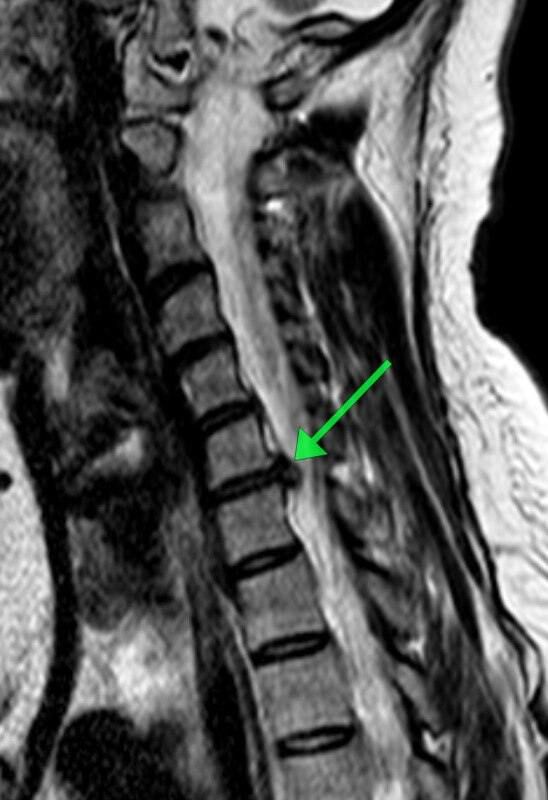

Пациентка обратилась с жлобами на изматывающую боль в руке. Ей провели МРТ, которое показало, что в шейном отделе сформировалась грыжа размером 8 мм. По словам медиков, образование сдавливало спинномозговой канал и корешковое отверстие, угрожая двигательной функции.

«Мы провели сложнейшее микрохирургическое вмешательство, в ходе которого удалили грыжу и стабилизировали позвоночник с помощью современного импланта», — рассказал нейрохирург Николай Карпов, отметив, что операция длилась два часа 20 минут.